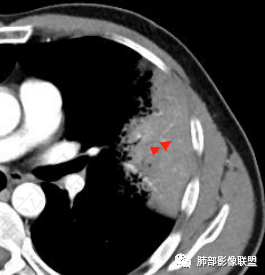

粘液有的,核位于基底部,胞浆粘液丰富

这种容易漂出去

这里看着像粘液里飘着脱离的肿瘤细胞团

这些含黏液细胞团,像是拍集体照,中间高两边矮一点,很符合粘液腺癌特点